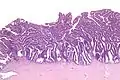

The name of the lesion describes it microscopic appearance. It has nipple-like structures with fibrovascular cores (papillae) that are long in relation to their width (villus-like), which are covered with a glandular pseudostratified columnar epithelium.

Very high magnification